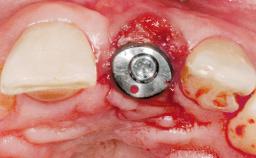

Late Placement of an Implant in a Maxillary Left Central Incisor Site

A 36-year-old female patient was referred for the replacement of the upper left central incisor (tooth 21), which had fractured. Although the tooth had been asymptomatic for many years, the crown began to loosen, at which time she presented to her dentist for an assessment. Teeth 21 and 22 had both been endodontically treated many years previously. She was a healthy individual and a non-smoker.

Type of Implants Two-Piece

Soft Tissue Grafting Simultaneous

Bone Volume Deficient horizontally, requiring prior grafting